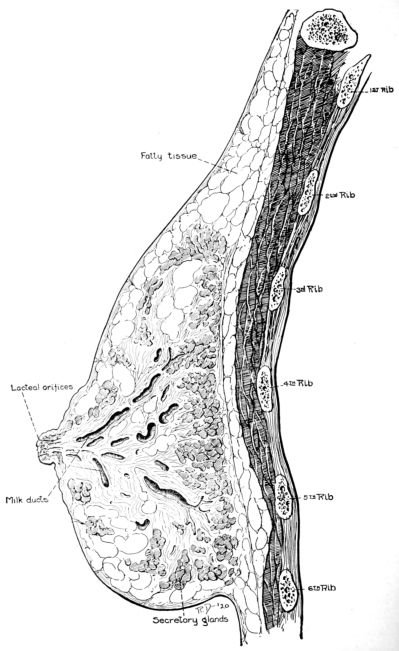

| 14. | Sagittal section of breast | 42 |

| 15. | Front view of breast | 43 |